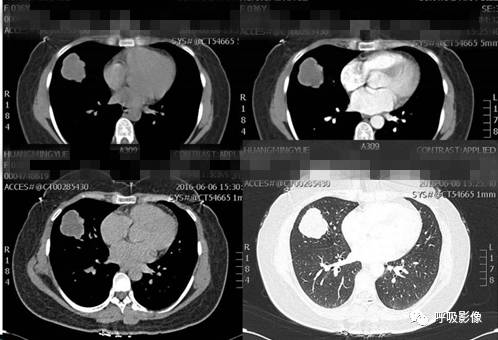

简单病史:女,43岁。咯血10余天。既往有子宫肌瘤切除病史。于山东省肿瘤医院查体,CT示:1.右侧附件区囊实性占位,同侧卵巢静脉显著增粗,考虑恶性肿瘤。2.双肺结节,考虑转移。3.宫体低密度灶,不除外子宫肌瘤。4.腹部、颈部扫描未见异常。子宫肌瘤病理切片会诊:子宫平滑肌瘤。盆腔附件包块穿刺活检细胞学检查示:查到可疑癌细胞。组织病理示:查见极少肿瘤细胞,考虑癌细胞。行紫杉醇联合卡铂化疗一疗程。

诊断依据:中年女性,有咯血病史。既往有子宫肌瘤切除病史。CT示右侧附件区囊实性占位,同侧卵巢静脉显著增粗,考虑恶性肿瘤。盆腔附件包块穿刺活检细胞学检查查到可疑癌细胞。病理示查见极少肿瘤细胞,考虑癌细胞。

胸部CT示双肺多发结节影,强化明显,内见明显坏死,提示血供丰富。

转移瘤多具有原发肿瘤特点,本例转移瘤为生殖源性肿瘤,盆腔附件包块穿刺活检细胞学检病理均查见恶性肿瘤细胞,结合转移灶坏死、强化明显,需考虑绒毛膜癌可能。

胸部CT双肺多发结节影,强化明显,内见明显坏死,提示血供丰富,这是诊断关键。